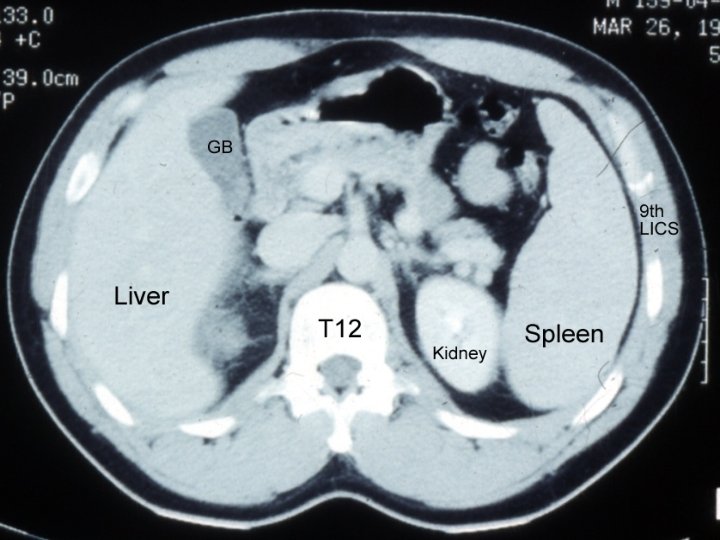

Investigation of the Spleen. FBC, Reticulocytes, tests for haemolysis. LFT & OGD in splenomegaly+portal hypertension in liver cirrhosis. Investigations for causes of splenomegaly including LN biopsy. Radiology: 1 -Calcification: splenic infarct, splenic a. aneurysm, hydatid cyst, TB. 2 -US, CT with contrast, MRI. 3 -Tc 99: is spleen site of RBC destruction? .

5. CT Modality of choice Used with contrast. Findings : 1. 2. 3. 4. Lacerations : irregular hypodense area with no enhancement. Sub-capsular hematoma : regular shape , cresentric. Intraparenchymal hematoma. Fragmentation with autosplenictomy.